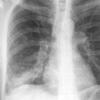

Case 4 RML pneum PA

Date: 04/16/2005

Views: 5398